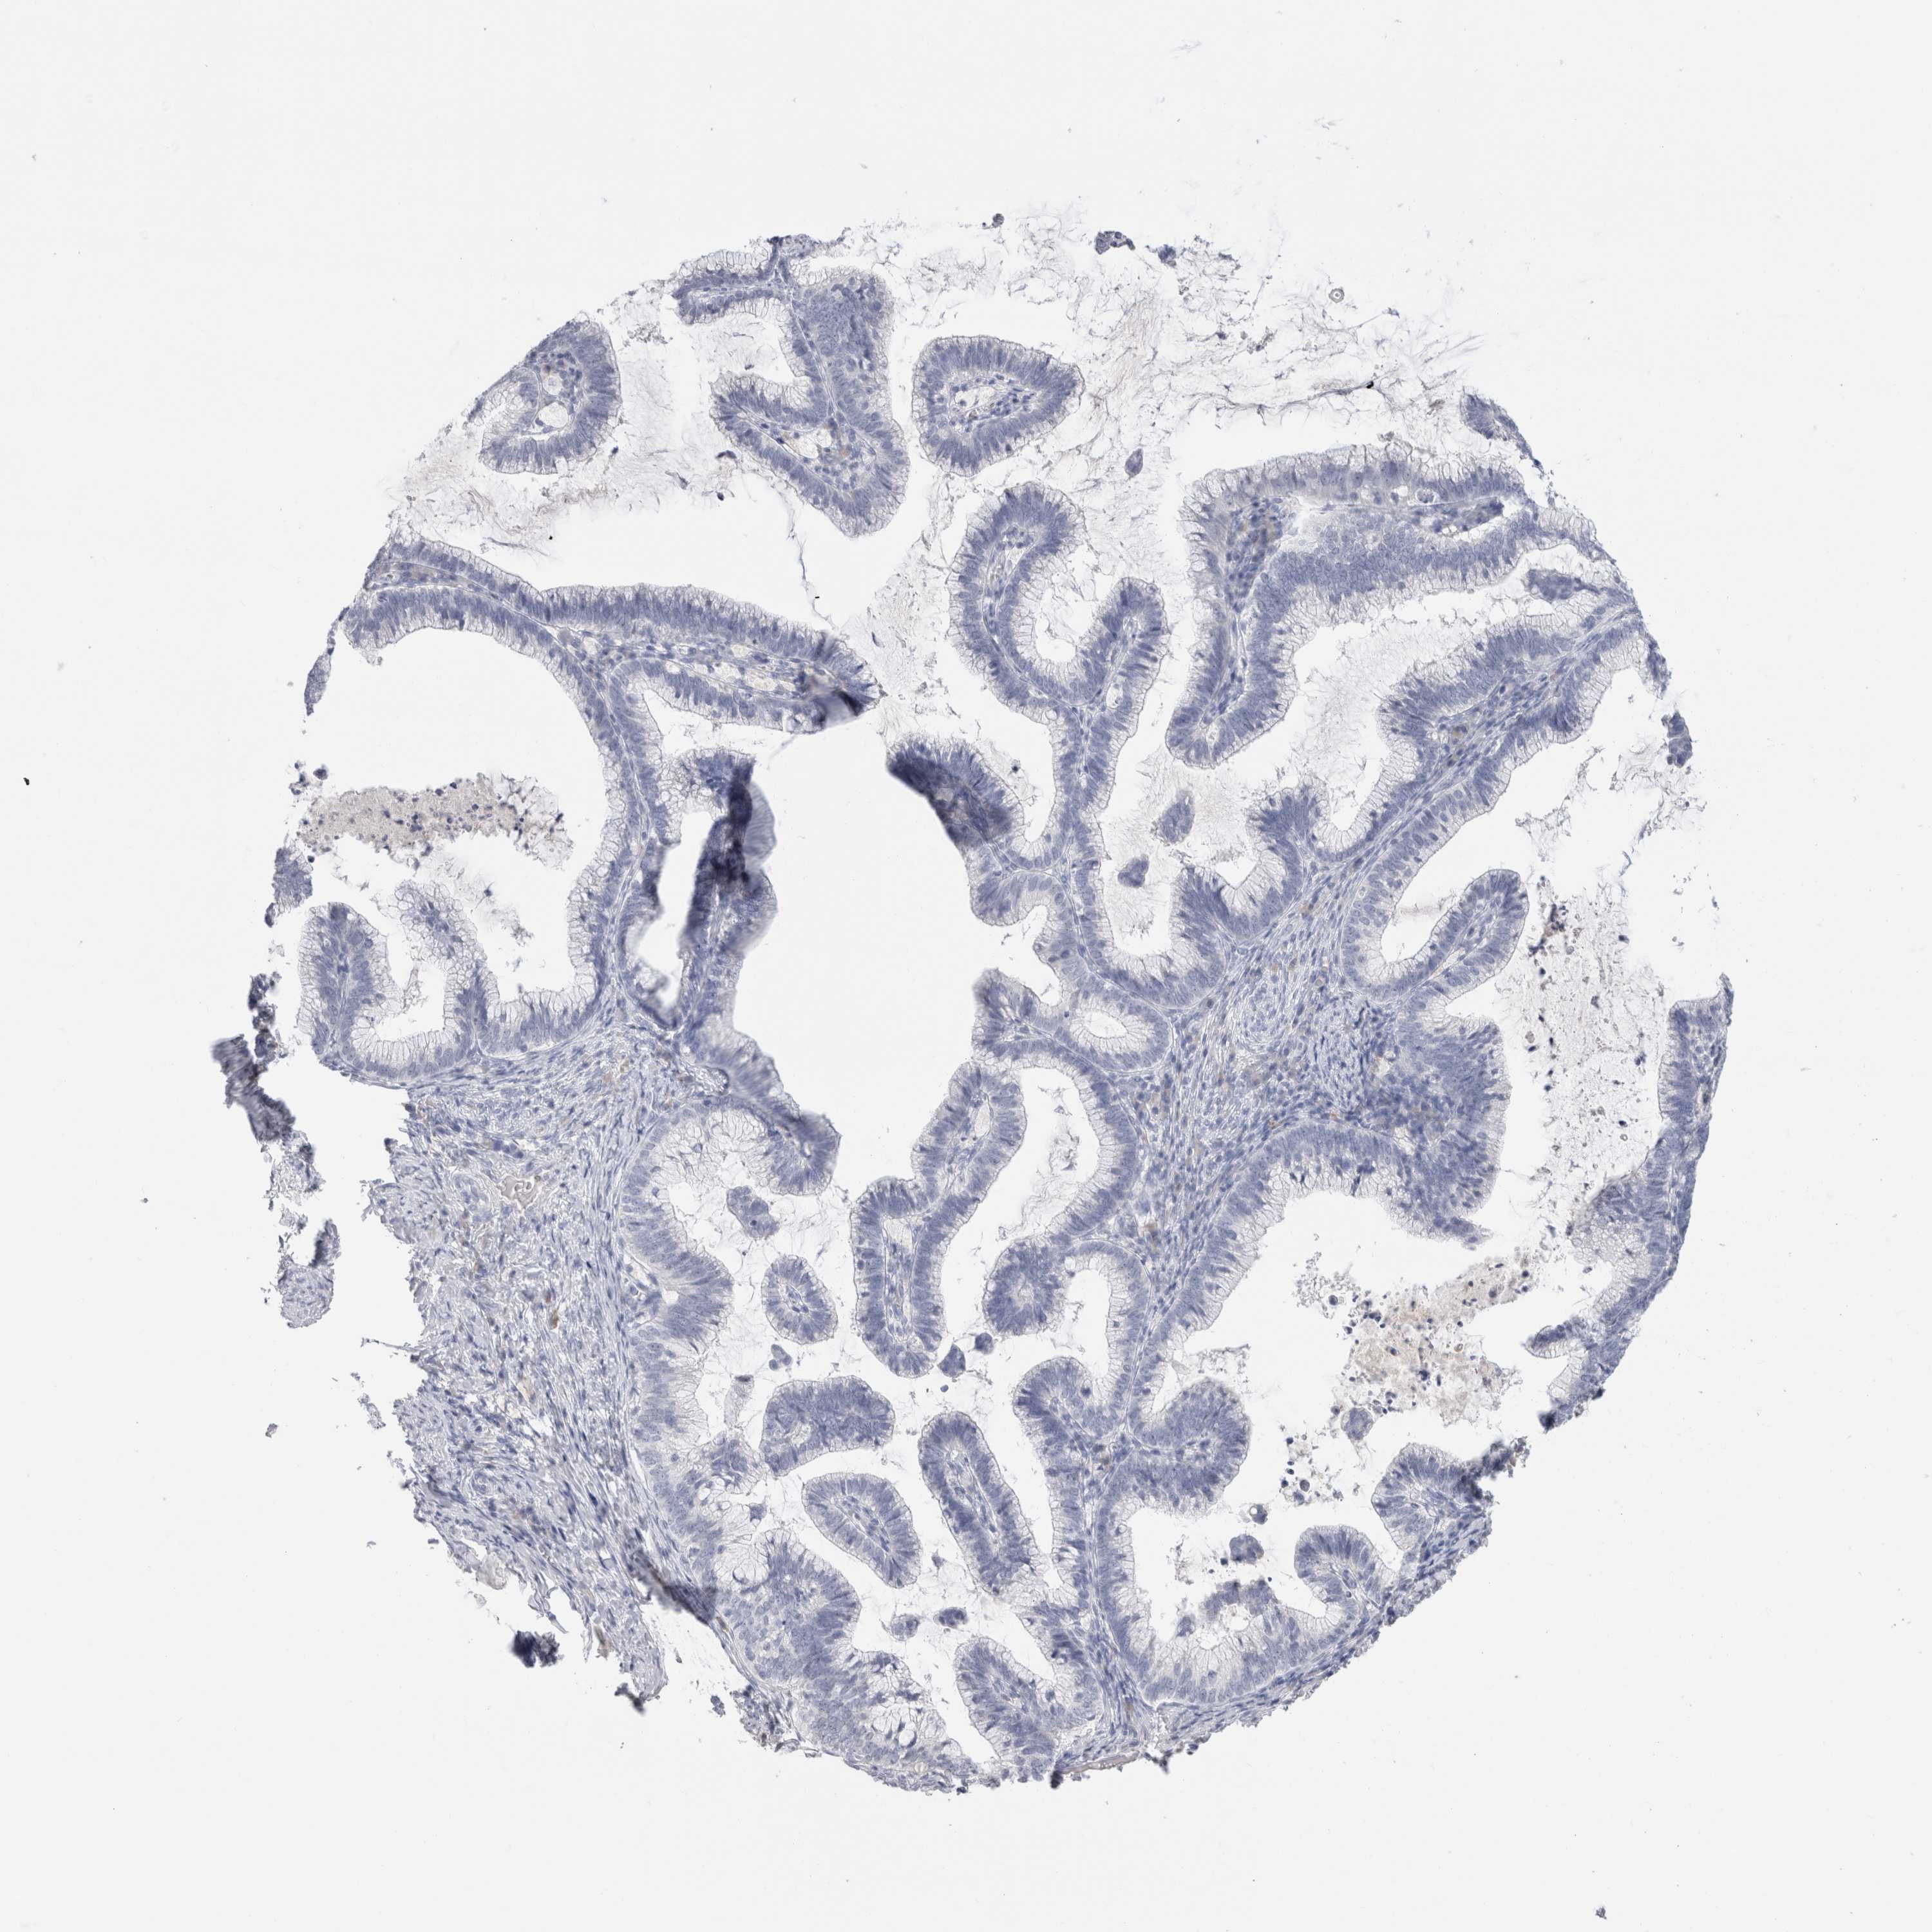

CERVICAL CANCER - Protein expressioni

A mouse-over function shows sample information and annotation data. Click on an image to view it in a full screen mode. Samples can be filtered based on level of antibody staining by selecting one or several of the following categories: high, medium, low and not detected. The assay and annotation is described here.

Note that samples used for immunohistochemistry by the Human Protein Atlas do not correspond to samples in the TCGA dataset.

Antibody stainingi

Antibody staining in the annotated cell types in the current human tissue is reported as not detected, low, medium, or high, based on conventional immunohistochemistry profiling in selected tissues. This score is based on the combination of the staining intensity and fraction of stained cells.

Each image is clickable and will lead to virtual microscopy that enables deeper exploration of all samples and also displays staining intensity scores, fraction scores and subcellular localization as well as patient and tissue information for each sample.

Antibody HPA051467

Antibody CAB025133

Squamous cell carcinoma, NOS

Adenocarcinoma, NOS